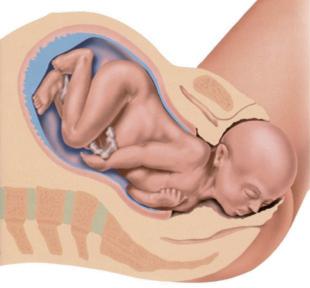

Der Embryo wächst in der Gebärmutter – die Zeit der Schwangerschaft

3. Monat: Der Embryo ist ca. 8 – 9 cm groß. Gesicht, Arme und Beine sind bereits entwickelt. Man nennt ihn jetzt Fetus.

5. Monat: Die Mutter kann das Strampeln des Fetus wahrnehmen. Auf dem Kopf beginnen Haare zu wachsen.

7. Monat: Der Fetus ist vollständig entwickelt. Er muss nur noch wachsen.

9. Monat: Die Entwicklung des Fetus ist abgeschlossen. Die Geburt kündigt sich durch ein Ziehen in der Gebärmutter (Wehen) an. Die Fruchtblase, in der der Fetus herangewachsen ist, platzt und das Fruchtwasser fließt aus.

Der heranwachsende Embryo oder Fetus ist über die Nabelschnur mit dem Mutterkuchen (der Plazenta) verbunden. So wird er mit allen lebensnotwendigen Nährstoffen und mit Sauerstoff aus dem Blut der Mutter versorgt.

Geburt:

Durch starkes Pressen wird das ca. 50 cm große Baby aus dem Bauch gepresst.